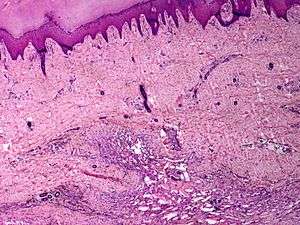

Skin angiomatosis

Angiomatosis is a non-neoplastic condition[1] presenting with little knots of capillaries in various organs. It consists of many angiomas.[2] It is associated with Von Hippel-Lindau Disease and is a rare genetic multi system disorder characterized by the abnormal growth of tumours in the body. Symptoms may include headaches, problems with balance and walking, dizziness, weakness of the limbs, vision problems and high blood pressure. Prognosis depends on the size and location of the tumour, untreated angiomatosis may lead to blindness and/ or permanent brain damage. Death may occur, with complications in the kidney or brain.[3]

These tend to be cavernous hemangiomas, which are sharply defined, sponge-like tumors composed of large, dilated, cavernous vascular spaces.